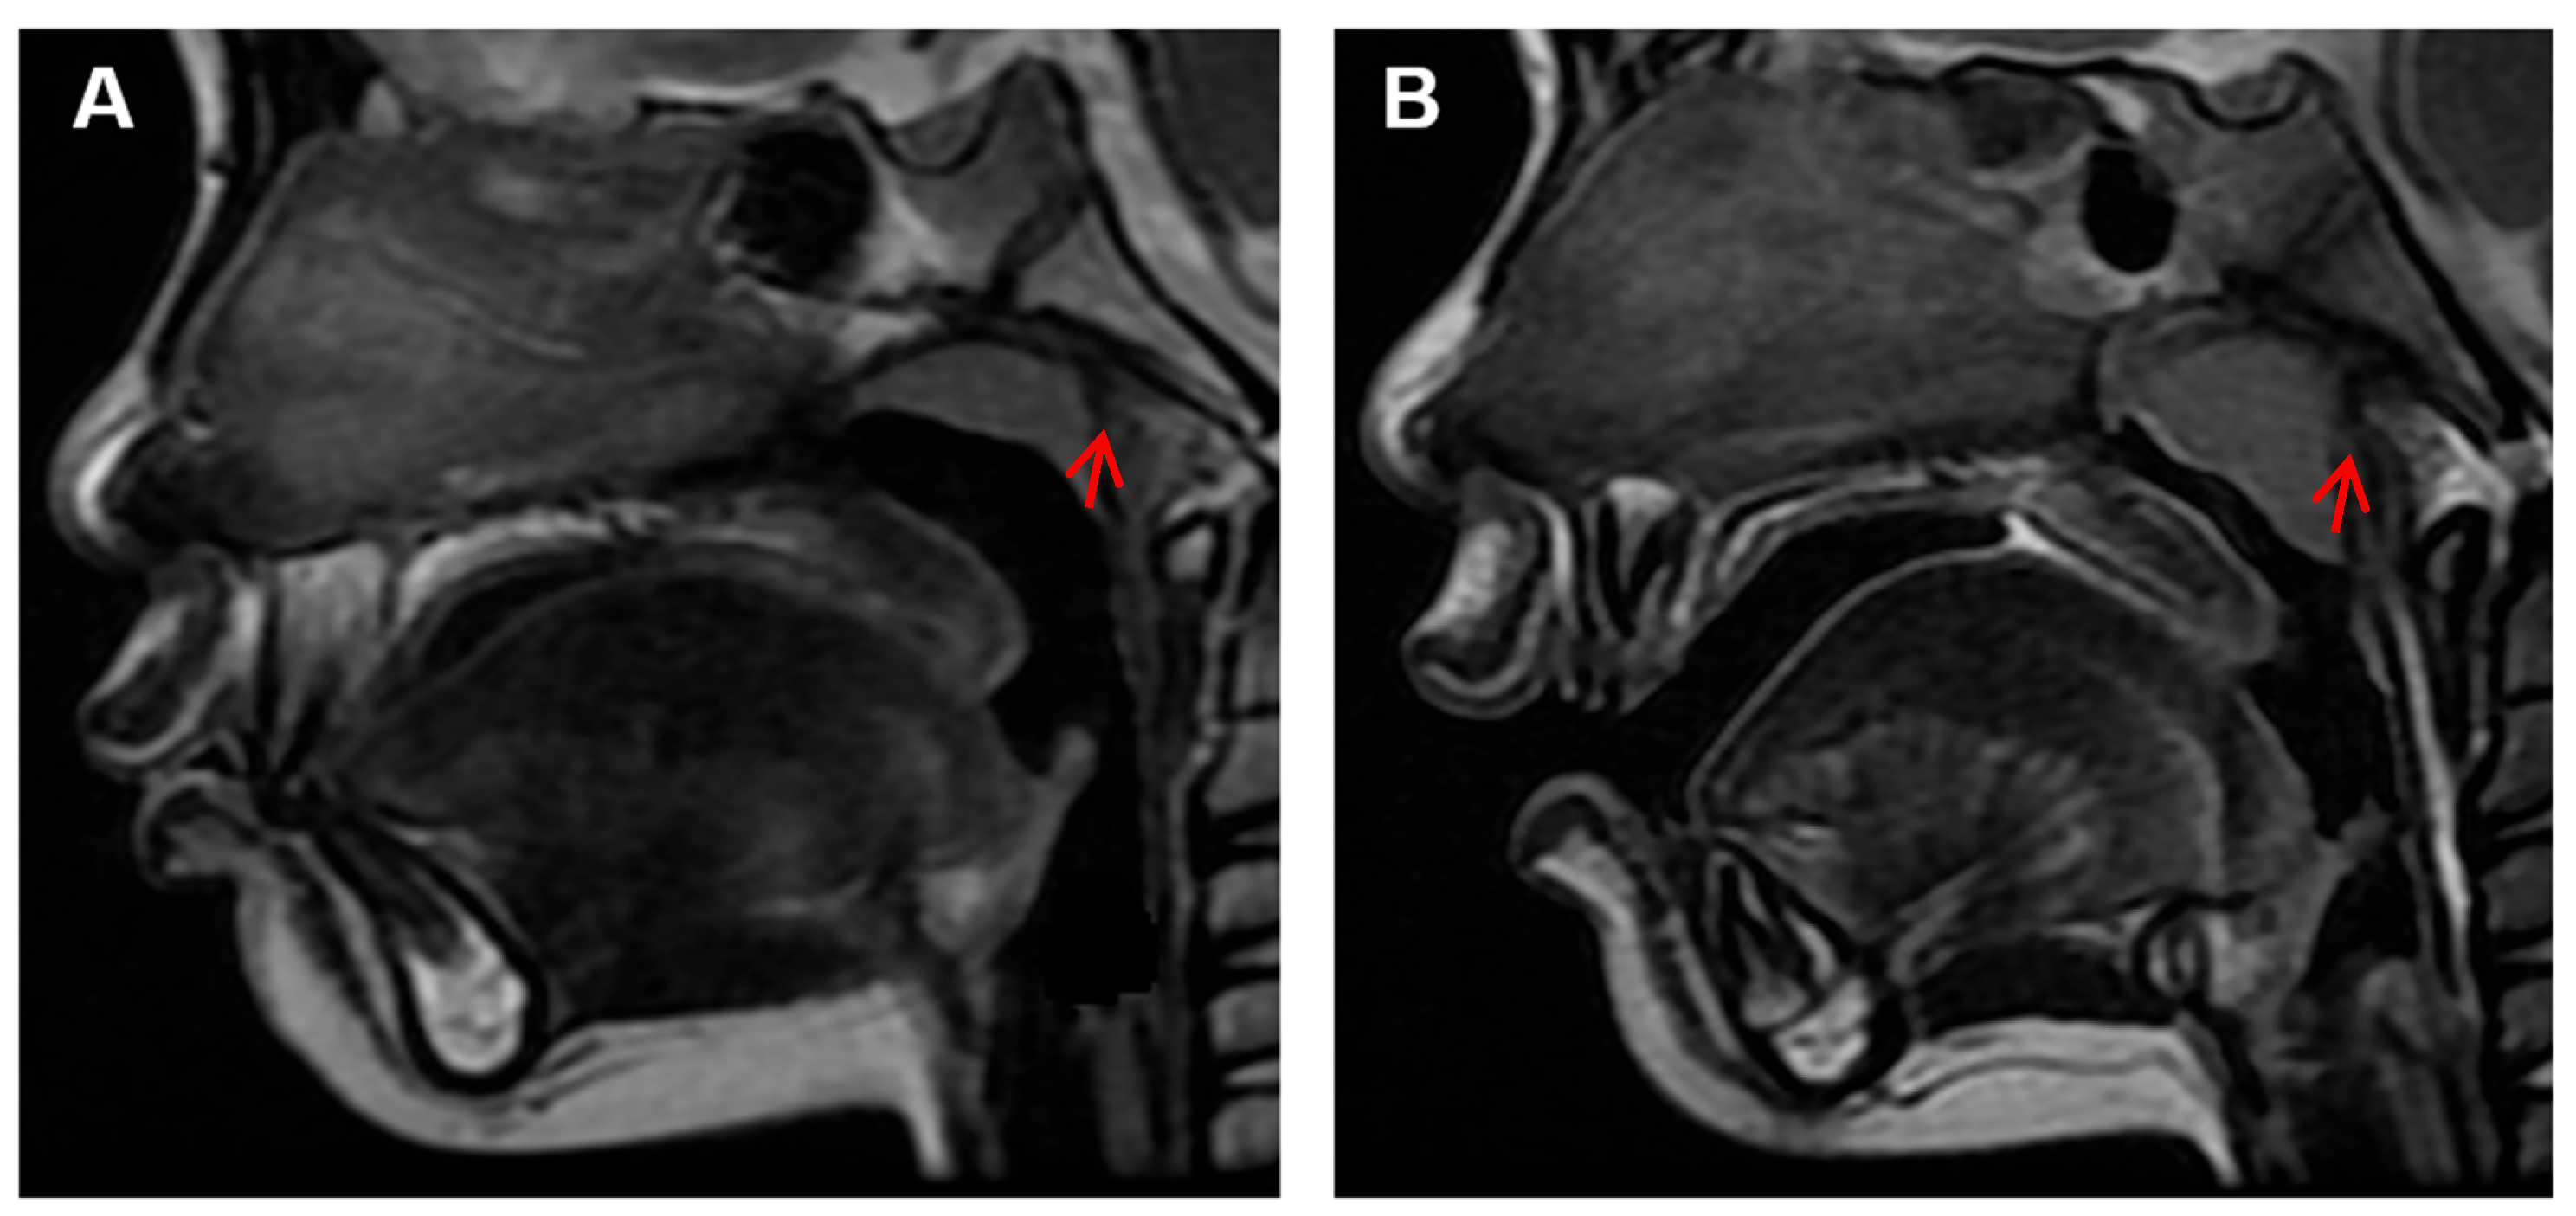

According to a previous study [15], the inclusion criteria were set as: (1) children who underwent MRI for reasons such as head trauma, febrile seizures, or suspected intracranial lesions, with no facial abnormalities other than adenoid hypertrophy, like nasal septum deviation, nasopharyngeal tumors, sinusitis, maxillary sinusitis, or delayed brain development; and (2) children with clear and complete mid-sagittal head MRI images in T2W1 signal (Figure 1).

Figure 5. MRI Images of normal and hypertrophic adenoids. (A) The red arrow indicates a normal adenoid; (B) The red arrow indicates a hypertrophic adenoid.